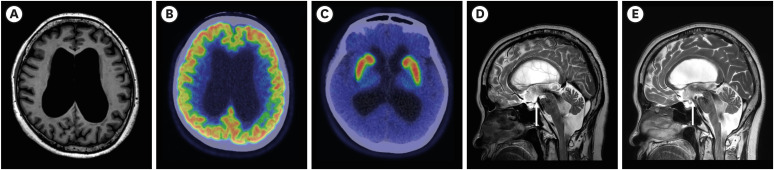

脑脊液(CSF)抽头试验后步态的改善是特发性常压脑积水(iNPH)患者进行分流手术的关键指标。然而,步态的定量分析需要复杂的设备和专家,这限制了实际应用。蓝牙连接传感器的发展为评估步态提供了一种经济实惠的方式。我们提出了一例iNPH患者,在干预前后使用智能鞋垫连续评估步态变化,这有助于临床决策。我们评估了一位68岁的女性,她表现出iNPH的三联症状(步态障碍、认知能力下降和尿频)。在脑脊液轻拍测试前后,使用带有四个压力传感器和加速度计的智能鞋垫以及常规时空参数对步态进行分析和比较。虽然在常规的步态参数测试前后没有观察到明显的变化,但从智能鞋垫收集的数据中发现了一些变化,包括改善了脚跟的打击,步伐的规律性和对称性。根据主观和客观的步态改善进行高级手术干预。术后3个月和6个月保持步态改善。我们的案例表明,易于使用的智能鞋垫可以通过提供额外的信息来辅助临床决策。

Improvement in gait after a cerebrospinal fluid (CSF) tap test is a key indicator for shunt surgery in idiopathic normal pressure hydrocephalus (iNPH) patients. However, quantitative analysis of gait requires sophisticated equipment and specialists that limit practical use. Development of Bluetooth-connected sensors offers affordable way to assess gait. We present a case of iNPH patient in whom gait changes were serially assessed using a smart insole before and after intervention, which helped in clinical decision making. A 68-year-old female who showed the triad of iNPH symptoms (gait disturbance, cognitive decline, and urinary frequency) were evaluated. Before and after the CSF tap test, gait was analyzed and compared using the smart insole with four pressure sensors and accelerometer, along with conventional spatiotemporal parameters. While no significant changes were observed between pre- and post-tap test in conventional parameters of gait, several changes were found in the data collected from the smart insole, including improved heel strike, step regularity and symmetry. Advanced surgical intervention was performed based on subjective and objective improvement in gait. The improved gait was maintained at 3 and 6 months after surgery. Our case showed that easy-to-use smart insoles could assist clinical decisions by providing additional information.